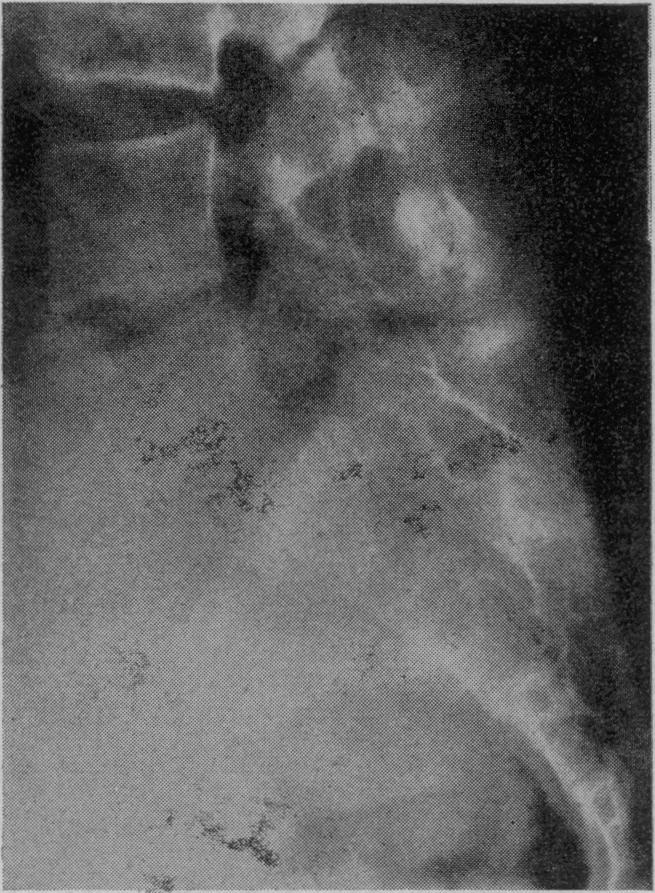

Lumbo-sacral fusion for low back pain.

Proc R Soc Med. 1956 Jul;49(7):401-5. doi: 10.1177/003591575604900706.